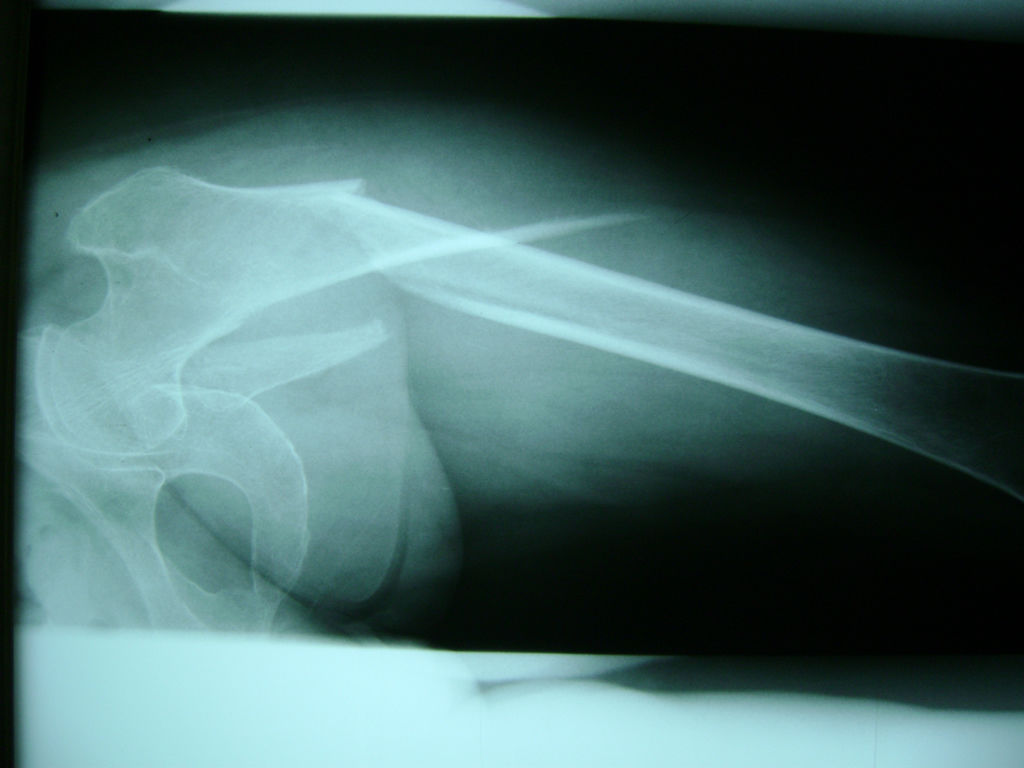

La cirugía de fractura de cadera se realiza para reparar una ruptura en la parte superior del hueso del muslo. Este hueso se denomina fémur.

Es parte de la articulación coxofemoral. Si una fractura de cadera no recibe tratamiento, es posible que deba permanecer en una silla o en la cama.

A menudo se recomienda la cirugía para reparar la fractura debido a dichos riesgos.